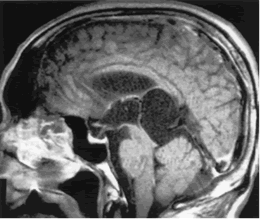

蛛網膜囊腫MRI表現CT 及 MRI 是蛛網膜囊腫最佳的診斷方法, 不但可以明確蛛網膜囊腫的部位、體積以及與周圍結構的關係,還能做出定性診斷。X線顯示蛛網膜囊腫鄰近骨質變薄、隆起或內板呈腦回壓跡樣凹陷等非特異性表現可作為輔助診斷。

2、MRI 檢查蛛網膜囊腫的特點為 T1 加權圖像示低信號,T2 加權像示高信號,與腦脊液信號相同。MRI 檢查可以了解病變與腦實質、腦池的關係,建立三維圖像,制定手術方案。鞘內注射造影對鑑別蛛網膜囊腫與其它囊性病變或腦池畸形有重要意義。用泛影葡胺造影, 蛛網膜囊腫被造影劑襯托出一圓形充盈缺損。MR 相位對比電影法可以有效了解腦脊液流通動力學,可鑑別蛛網膜囊腫和蛛網膜下腔擴張,也可了解囊腫與蛛網膜下腔交通情況,較鞘內造影檢查具有無創、準確性高的優點。